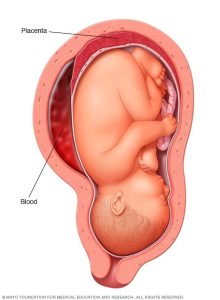

Ingobyi ( placenta)

Ni urutiriro rw’inda rufasha umwana kubona amaraso, intungamubiri, n’umwuka. Placenta ikunze kwifata ku rukuta rw’inyababyeyi (uterine wall), cyane cyane mu gice cyo hejuru cy’inyababyeyi (fundus) cyangwa inyuma (posterior wall). Aha ni ho haba amaraso menshi, bikayiha ubushobozi bwo guha umwana ibiryo n’umwuka.

Kuba placenta ikunze kwifata hejuru cyangwa inyuma bituma inzira y’umwana (inkondo y’umura) idahagarikwa, bityo kubyara bikagenda neza.

2- Placenta itameze neza:Placenta iba ishobora kuba ifashe nabi kuri nyababyeyi cyangwa ikaba iri hasi cyane (placenta previa), ishobora kubuza inzira y’umwana cyangwa gutera kuva. Iyo itandukanye hakiri kare (placental abruption), bishobora gushyira ubuzima mu kaga. Ubusanzwe placenta isohoka…

Ni ikibazo gikomeye aho umubyeyi atakaza amaraso menshi nyuma yo kubyara. Akenshi giterwa na nyababyeyi idakomeye (uterine atony), aho nyababyeyi inanirwa gukomera no kuzirika imitsi y’amaraso nyuma yo gusohora placenta. Ibi bishobora guterwa no kubyarira igihe kirekire kuba inda yari nini, cyangwa kuba umubyeyi yarabyaye inshuro nyinshi. Hari n’igihe placenta isigaye imbere cyangwa ikitandukanya kare, byose bikongera ibyago byo kuva.

– Placenta ifashe nabi cyangwa ikitandukanya kare: Iyo placenta iri hasi cyane (placenta previa) cyangwa ikitandukanya hakiri kare (placental abruption), umwana ashobora kubura umwuka.

4. Placenta previa cyangwa abruption

– Placenta previa: Placenta iri hasi cyaneyitambikaa inzira y’umwana, bikaba bigoye kumusohora.

– Placental abruption: Igihe Placenta yitandukanya hakiri kare, bigatera kuva cyane no kubuza umwana umwuka. Ibi bibazo byombi bishobora gushyira ubuzima bw’umubyeyi n’umwana mu kaga.